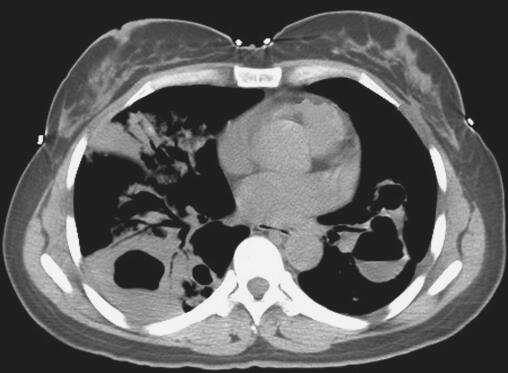

患者入院后考虑肺囊肿继发感染,给予抗感染治疗,完善相关检查,血常规:WBC 11.19×109/L,N% 68.90%;肺肿瘤标志物:CEA 2.46ng/ml,CYFRA 4.34ng/ml,NSE 9.38ng/ml;胸部CT示双肺气液囊肿并感染可能(图1);绒毛膜促性腺激素(β)HCG-BETA 5.48mIU/ml;电子支气管镜镜检未见异常;电子支气管镜肺活检病理示:子宫胎盘部位滋养细胞肿瘤肺转移。

图1 肺CT示双肺气液囊肿并感染可能

此例患者胸部CT提示双侧肺野多发液气囊性改变,考虑与滋养细胞在肺内破坏血管壁进入肺泡,使周围组织发生炎性浸润、出血、水肿,各肺泡病变融合成团,中心坏死,形成囊肿样改变,同时滋养细胞进入呼吸性细支气管为中心的细支气管周围组织发生炎性浸润,使呼吸性细支气管狭窄、闭塞,当囊肿内黏液潴留过多,或继发化脓性感染时,囊腔易与呼吸性细支气管穿透,形成单向性活瓣样通气,从而导致囊腔内压力不断升高,形成张力性液气囊肿改变。